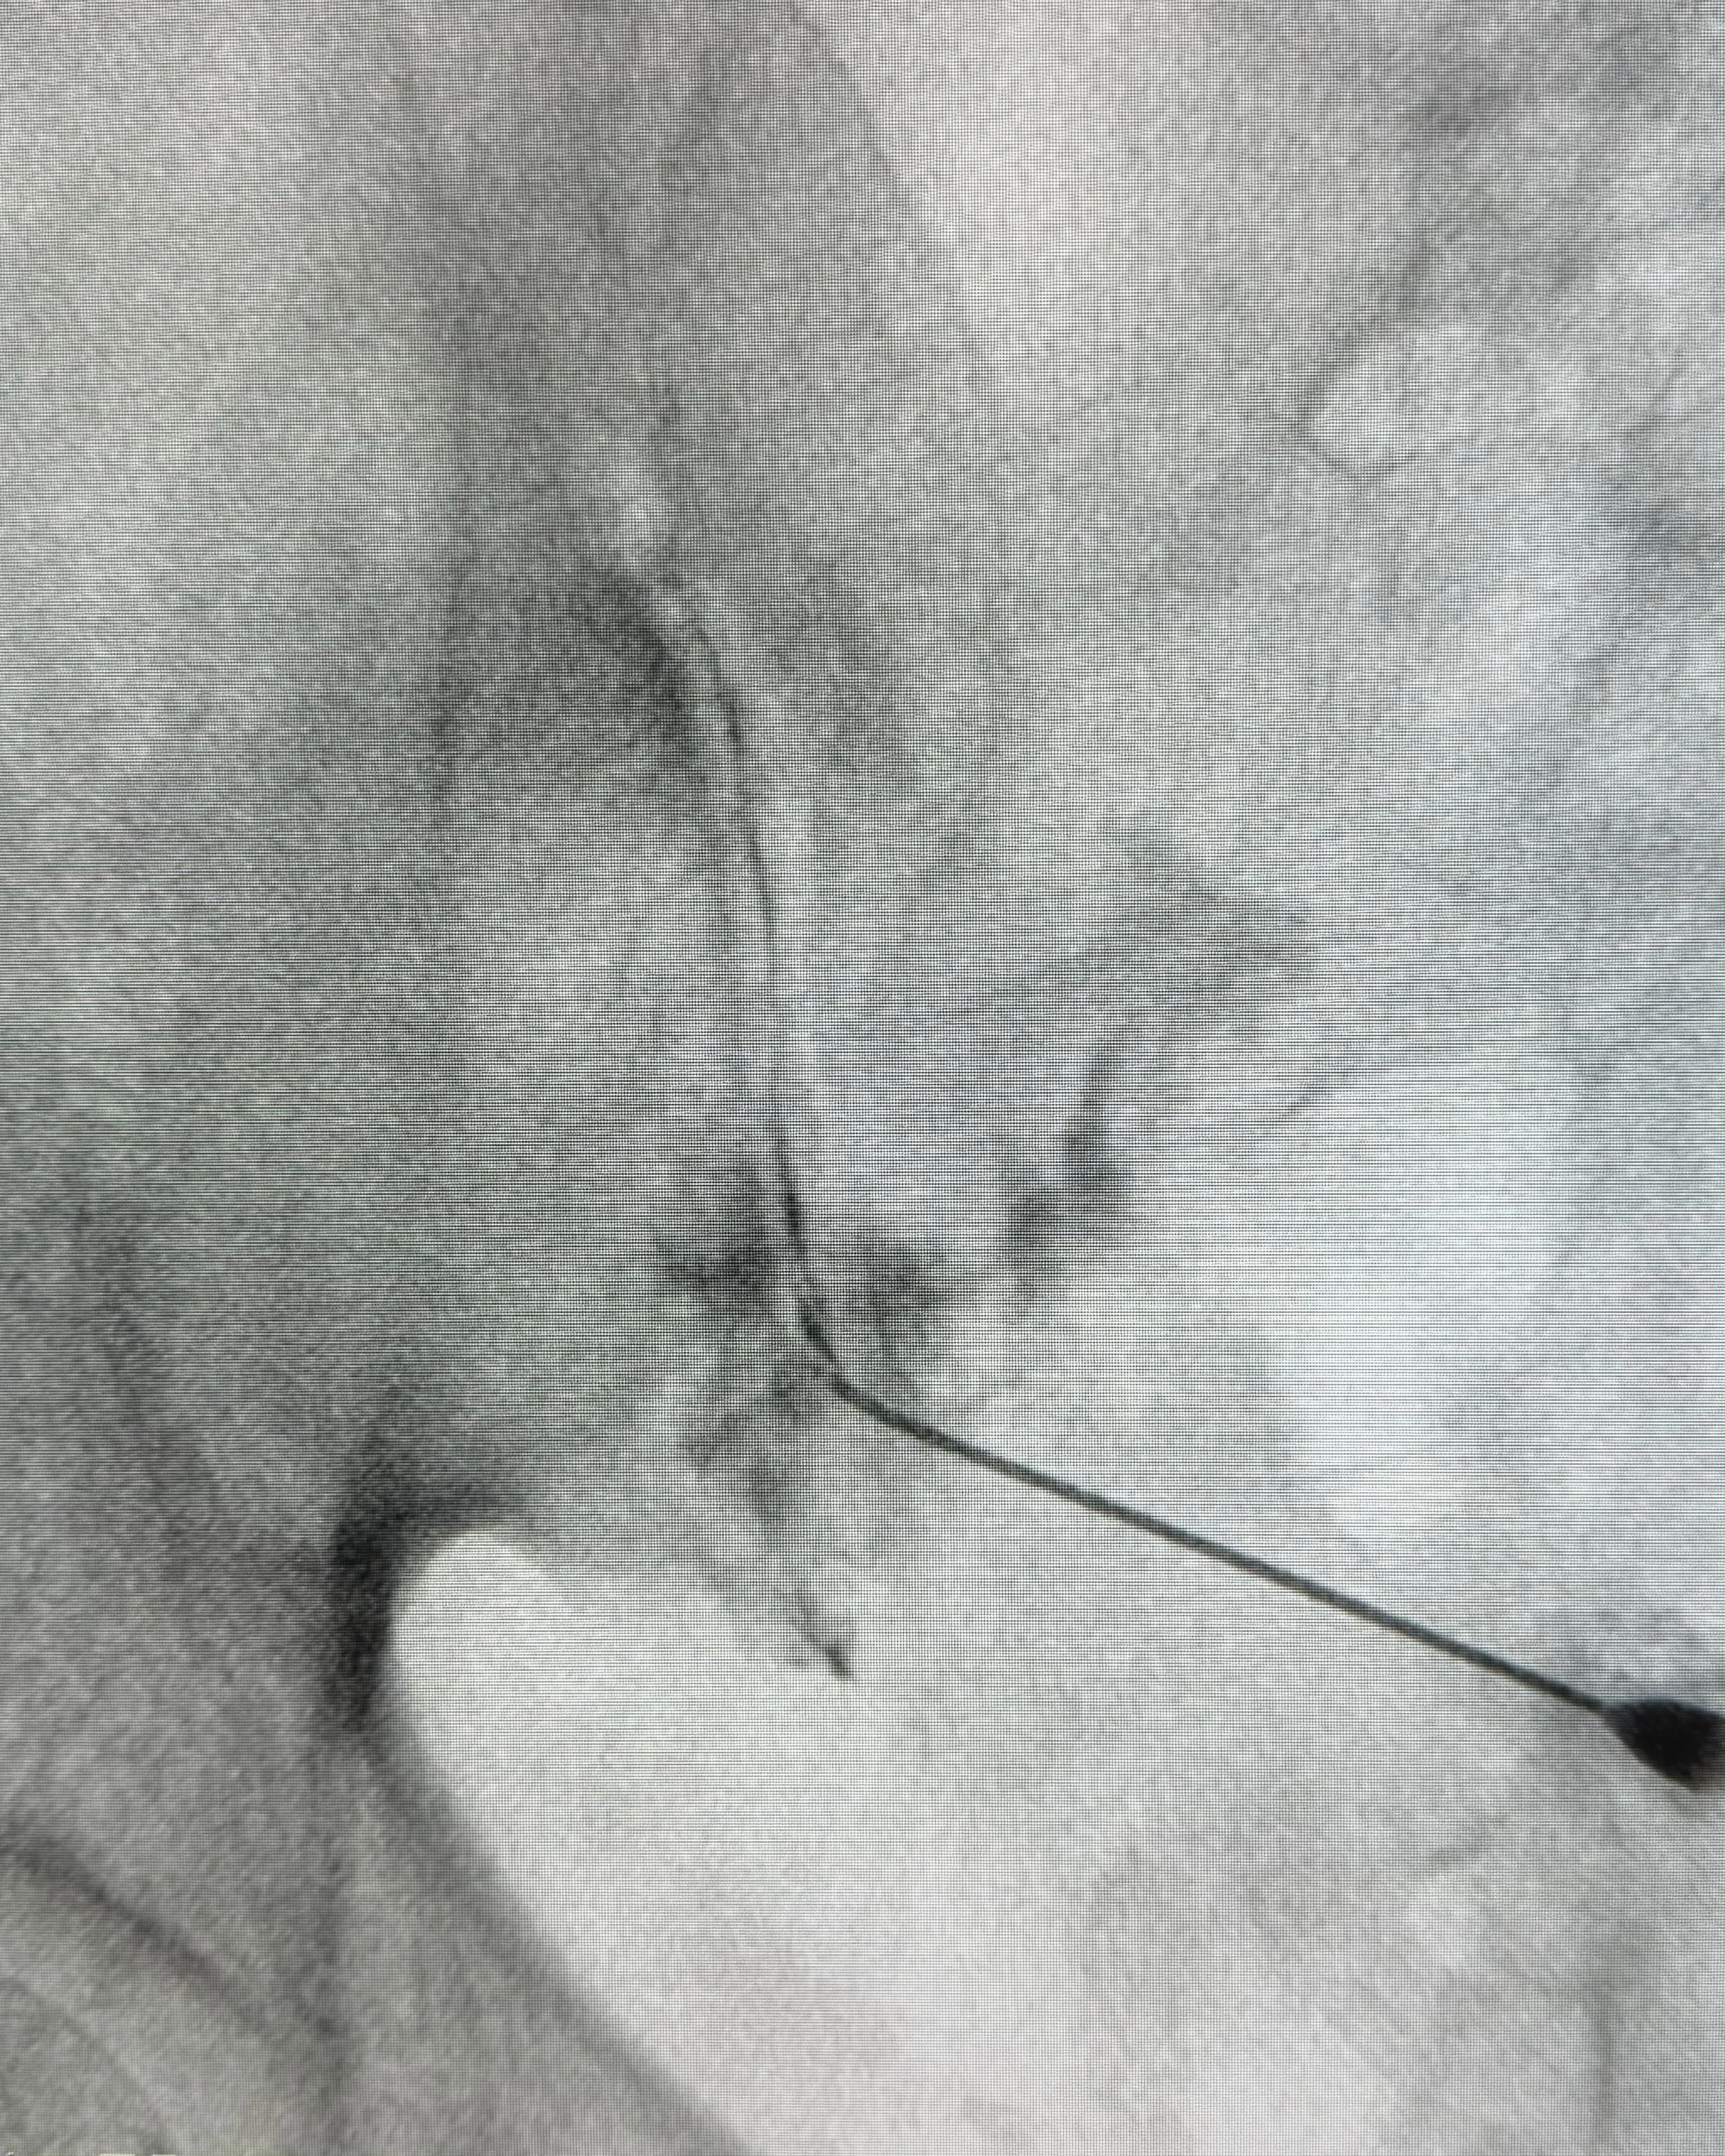

3. Injection: Using fluoroscopic guidance, a needle is carefully inserted into the sacroiliac joint, and the medication mixture is injected to provide pain relief and reduce inflammation.